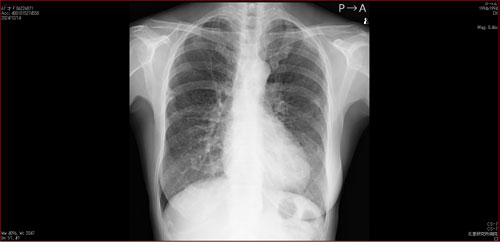

肺X線画像

- 2023.09.21 入院加療の必要ありと診断された画像(国立系病院)